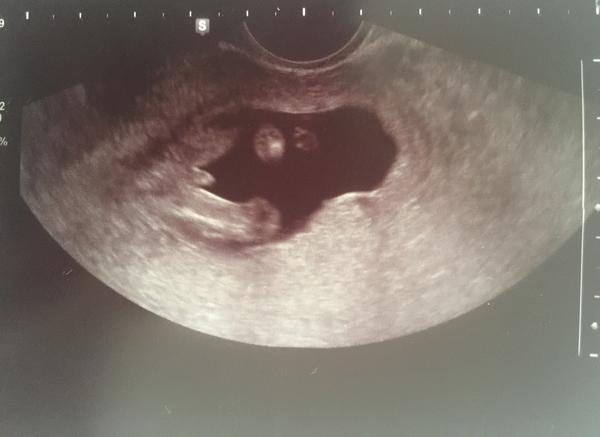

@estrellita to me taky napadlo, ale zase si říkám jestli to není pupecnik a to nic dole odpovídá kavovemu zrnu 🙂 já nevím, je to hrozné, ale musíme tedy ještě počkat do úterý 😉 ale díky moc za tip, já stále budu věřit, že to zůstane holčička 😀